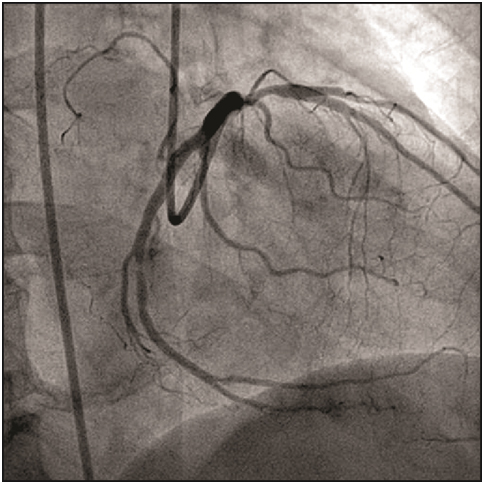

A 7F Judkins guiding catheter (Cordis Corp., Florida, USA) was used to cannulate the left coronary artery, and the lesion was crossed by using 0.014”Floppy guidewire (Abbott Vascular Inc., California, USA). We experienced that the movement of the wire tip became restricted after it crossed, the lesion. Angiograms in different views showed that the distal tip of wire was trapped in a small branch of the left circumflex coronary artery [Table/Fig-1], which had gone into spasm. Immediately, nitroglycerin, sodium nitroprusside, and nicorandil were given to relieve the spasm. Repeated attempts were made to gently pull the wire, but the guiding catheter was getting sucked in to the left circumflex coronary artery and also the guidewire did not move at all. Later, the spring over the wire got uncoiled [Table/Fig-2] and the radio-opaque tip got fragmented upon increasing the pressure over the wire. The two portions were being held together by the fine uncoiled spring coating. At that point, we passed a noncompliant Sprinter balloon (Medtronic Inc., Minnesota, USA) of 1.5 X 10 mm size to the distal tip of the wire and tried to pull the wire gently, but this caused further uncoiling of the wire and the wire could not be retrieved. To tide over the crisis, we used a simple indigenous way of retrieval using a bare noncompliant balloon of 2.5X 9 mm size, which was passed up to the tip of guiding catheter [Table/Fig-3]. The balloon was inflated at 10 atm pressure inside the tip of guiding catheter, which led to successful entrapment of the guidewire between outer surface of the balloon and inner wall of the guiding catheter. Once the wire was secured properly, whole assembly was removed en masse through the vascular system [Table/Fig-4,5 and 6].

Check angio ensured that no fragments were left in the vascular system; displaying 80% stenosis in the left circumflex artery